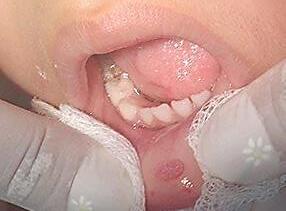

Presentación de caso clínico

Paciente femenino de 10 años de edadacudeaconsultaporlesionesmúltiples en la mucosa; de superficie rugosa, firme y

con un tiempo de evolución de tres años, refierequesuhermanamayortuvolesiones similares. (Fig. 7 y 8), se toma biopsia de una de las lesiones donde se observa presencia de paraqueratosis, hiperplasia epitelialconacantosisyanastomosisclavos epiteliales.

Fig.7 y 8

Hiperplasia epitelial multifocal, imagen clínica

Nota:Fototomadaporelautor

Algunosqueratinocitossuperficiales muestran un cambio coilocítico, también conocido como mitosoide (Fig 9). Después de entregar el diagnóstico de patología se recomendó imiquimod al 5 % para el resto de las lesiones las cuales fueron disminuyendopaulatinamente.